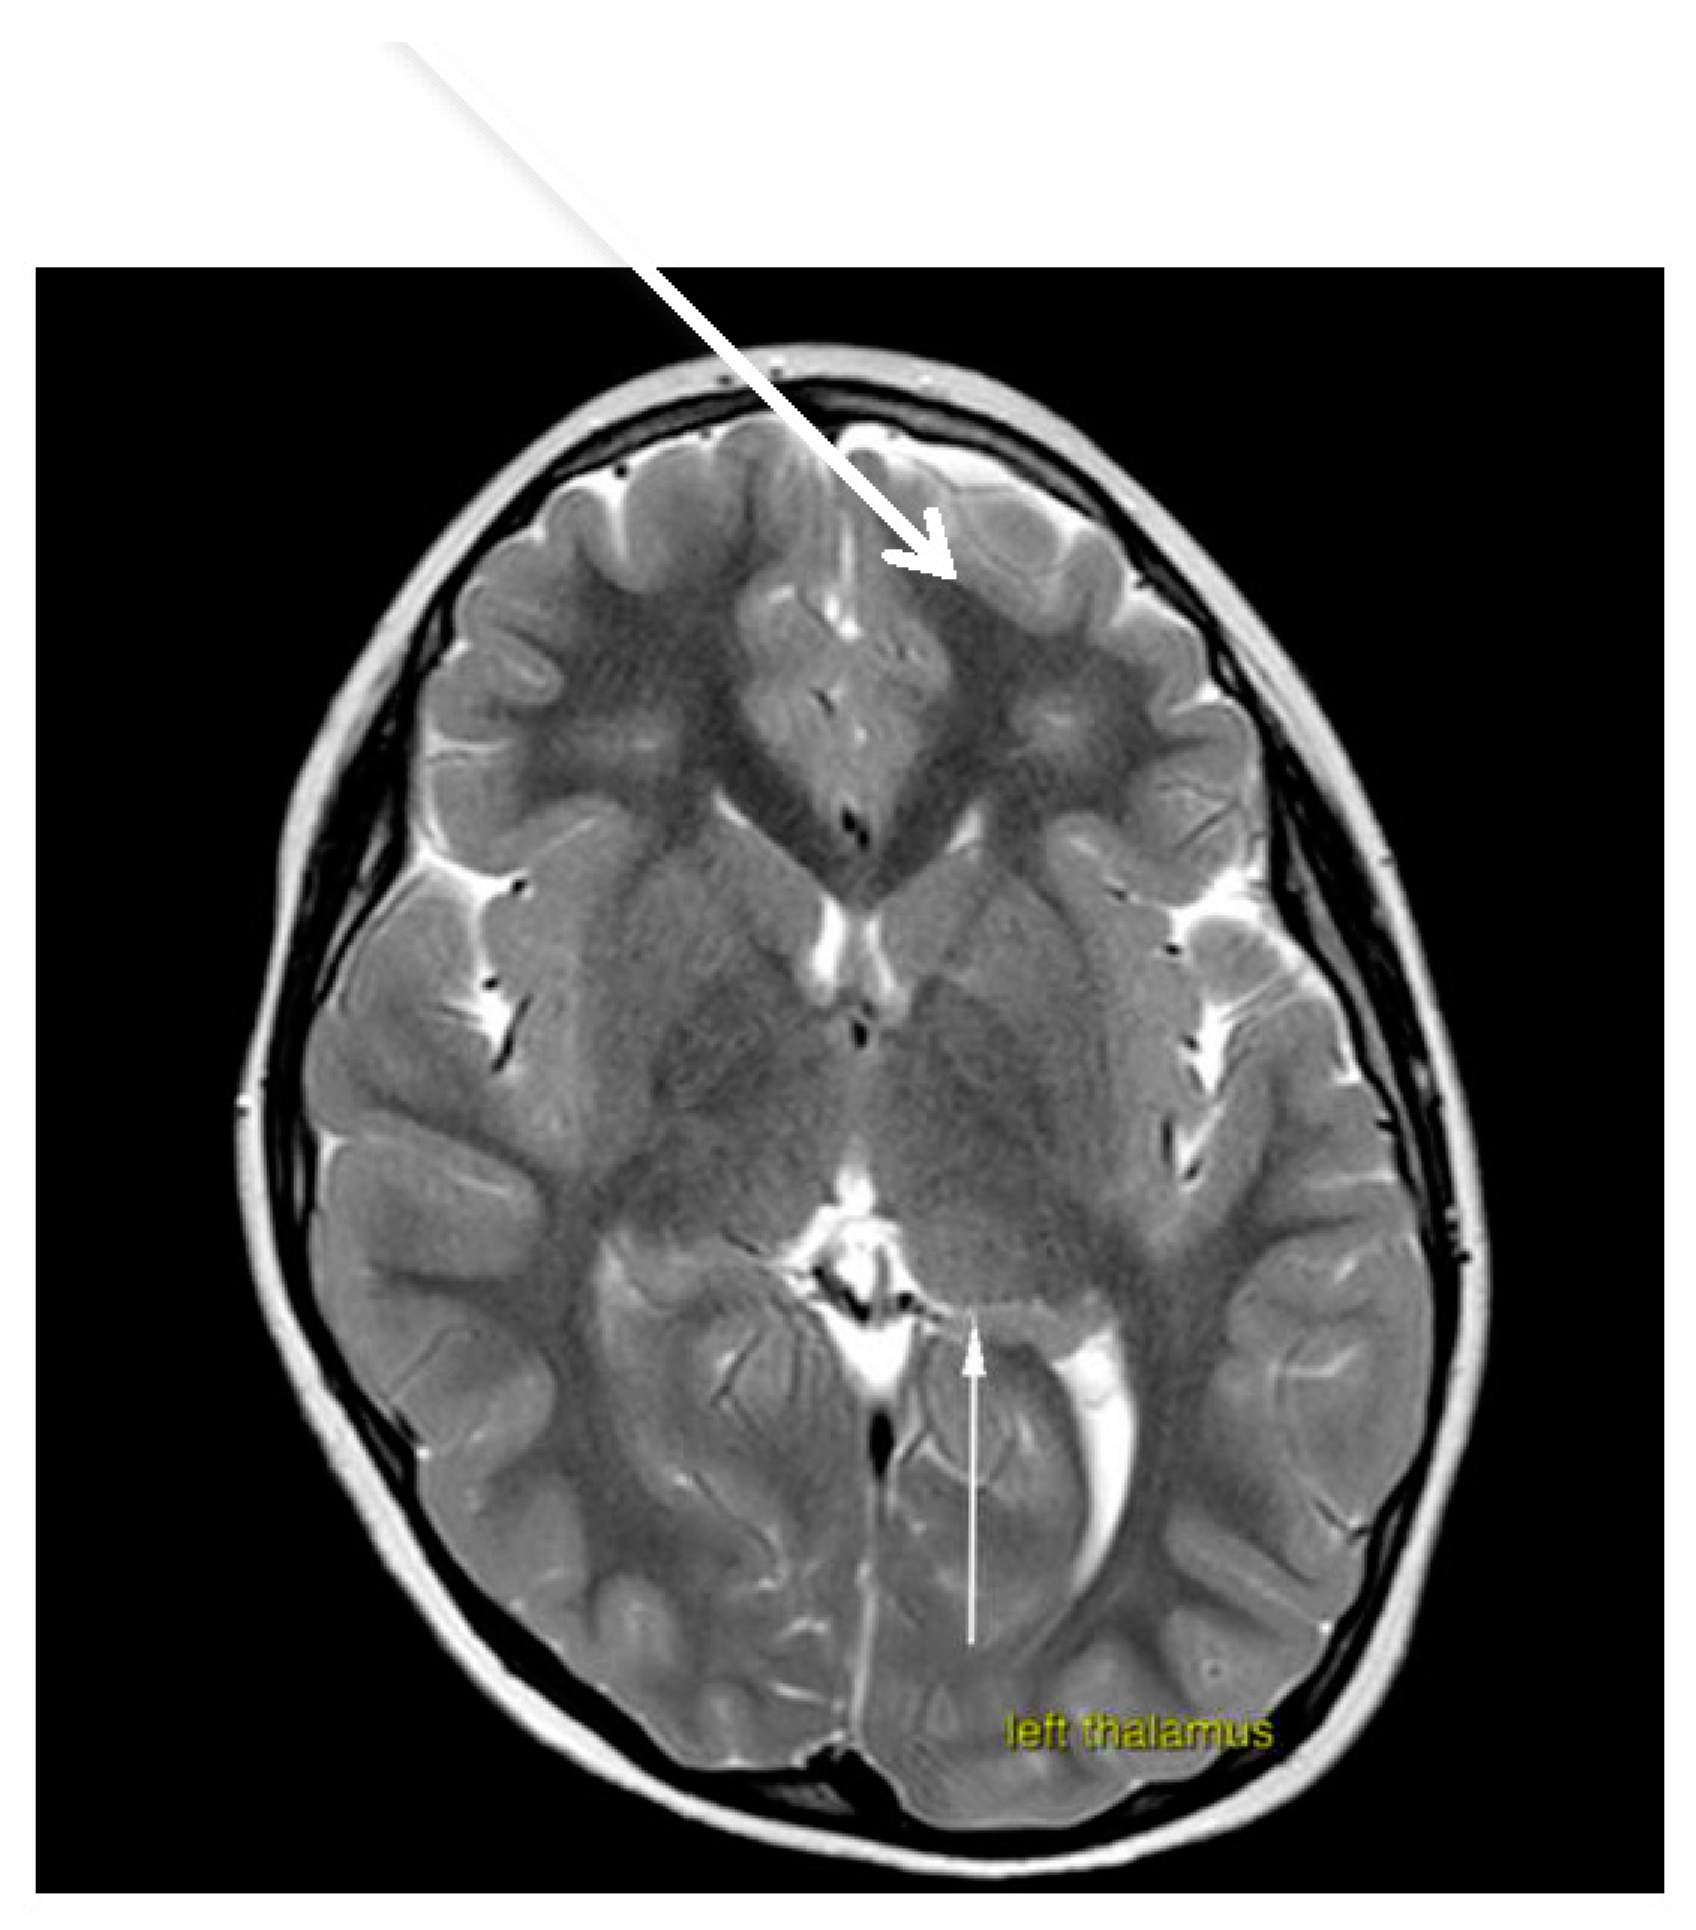

Brain magnetic resonance imaging (MRI) demonstrated hypoplasia of the brainstem (Figure 2), a left thalamus volume larger than the right (Figure 3), an enlarged fourth ventricle, an anterior and posterior midline bulbar and pontine cleft (split-pons sign) (Figure 4), a butterfly configuration of the medulla (Figure 5), an occipital and parietal plagiocephaly on the right side, and a slight benign enlargement of the subarachnoid spaces in the frontotemporal area. There were no signal changes within the medulla or pons in any of the brain MRI sequences.

Figure 3. MRI brain imaging shows that the volume of the left thalamus is larger than the right.